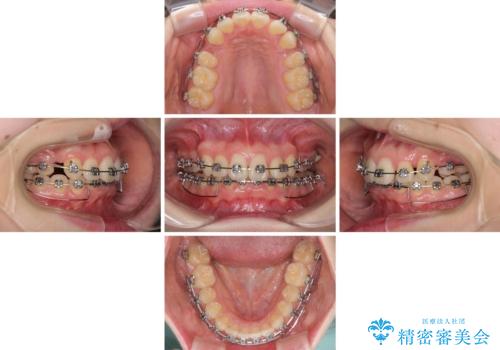

- 矯正装置

- メタルブラケット

奥歯の咬み合わせがなかなか定まらず、スペースが閉じるまでに時間がかかりましたが、最終的には正中を合わせることもできました。